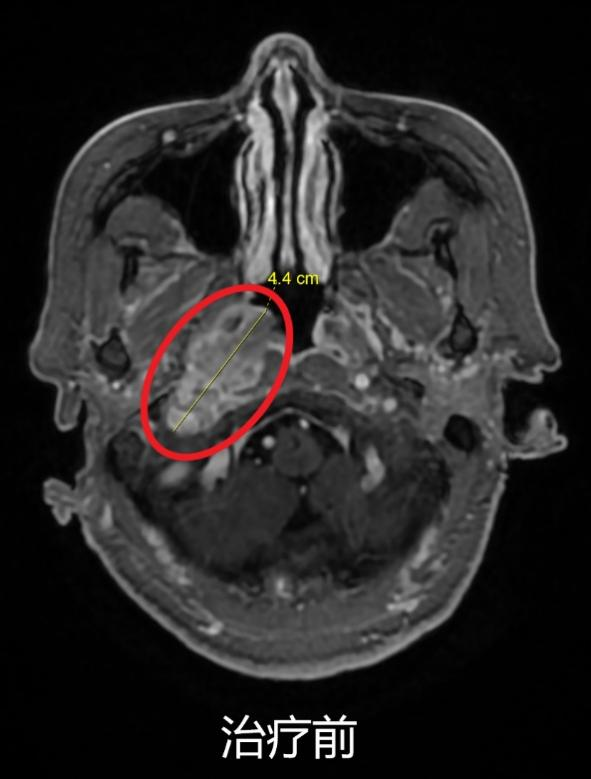

同步放化療(鼻咽癌伴頸部淋巴結轉移)